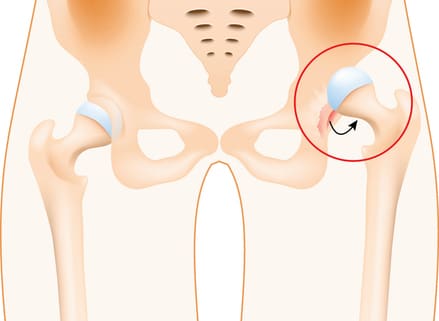

Your hip is a ball and socket joint making it one of our most flexible joints, hence allowing greater range of motion than almost every other joint in the body, sans the shoulder. A smooth tissue, the articular cartilage, covers the surface of the ball and the socket. It creates a low friction surface that helps the bones glide easily across each other. The acetabulum is surrounded by strong fibrocartilage called the labrum. The labrum forms a lining around the socket, creating a tight seal, helping to provide stability to the hip joint

What is A Hip Dislocation?

A traumatic hip dislocation occurs when the head of the thigh bone (femur) is forced out of its socket in the hip bone (pelvis). When there is a hip dislocation, the femoral head is pushed either backward out of the socket, or forward. It typically takes a major force, like a fall, to dislocate the hip. Car collisions and falls from significant heights are common causes and, as a result, other injuries like broken bones often occur with the dislocation. A hip dislocation is a serious medical emergency, where immediate treatment is necessary.